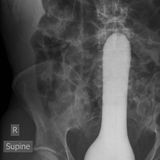

Diese Dinge gehören dort eigentlich nicht hin: Immer wieder passieren Unfälle, wenn Menschen sich zur sexuellen Stimulation über den After Gegenstände in den Darm einführen. Ob Orangen, Spraydosen oder Kaffeebüchsen - der Fantasie sind dabei offenbar keine Grenzen gesetzt.

Die Webseite radiopaedia.org zeigt, welche Dinge Ärzte auf Röntgenbildern schon entdeckt haben. Die Aufnahmen wirken skurril und erschreckend zugleich und machen deutlich, wie weit die eingeführten Dinge bereits in den mescnhlichen Darm vordringen können.

Aber Glück im Unglück für die Patienten: Die Gegenstände können meist ohne Operation entfernt werden. Sehen Sie hier einige der spektakulärsten Röntgenaufnahmen. Da runzeln selbst Chirurgen die Stirn.